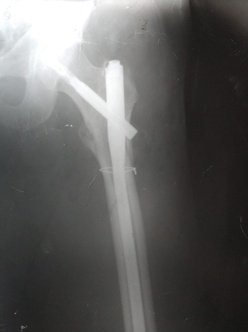

При огляді: положення хворого пасивне на каталці, біль в області в\3 правої стегнової кістки та кульшового суглобу що посилюється при пальпації та спробі рухів у суглобі. Крепітація уламків. Права н\кінцівка ротована до зовні. Позитивний симптом «прилиплої п’яти». Проведено рентгенографію правої стегнової кістки з кульшовим суглобом. Встановлено діагноз: Закритий уламковий, черезвертельний перелом правої стегнової кістки (Клас АО 31.А2.2) зі зміщенням.

Хворий госпіталізований в травматологічне відділення для подальшого дообстеження та оперативного лікування. З метою тимчасової фіксації, тракції та зменшення больового синдрому накладено систему скелетного витяжіння. В умовах травматологічного відділення хворий був дообстежений та оглянута суміжними спеціалістами терапевтом, кардіологом, анестезіологом.

Протягом 32 годин від отримання травми хворий був прооперований. Операція: Закрита репозиція з металоостеосинтезом перелому 31.А2.2 проксимальним стегновим стрижнем PFN-A. Після оперативного втручання хворий перебував під наглядом у відділенні інтенсивної терапії. На 2гу добу хворий переведена в травматологічне відділення. В травматологічному відділення хворому під наглядом лікуючого лікаря було дозволено сідати у ліжку. На 3 тю добу хворий під наглядом лікуючого лікаря з допомогою вставав. На 4-ту добу пересувався біля ліжка в палаті. На 5 ту-10ту добу хворий пересувався з допомогою в ходунках в межах палати. На 12 ту добу знято шви з рани. Хворий в задовільному стані виписаний з травматологічного відділення. На амбулаторне лікування. Надано рекомендації з приводу подальшого лікування в амбулаторних умовах.